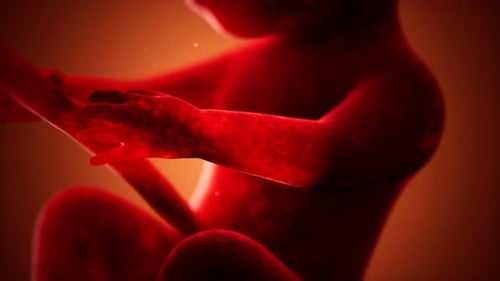

Animation médicale 3D d'un foetus humain

- Longueur

- 0:19

- Résolution

- 4096 x 2304

- Taux de cadre

- 30 fps